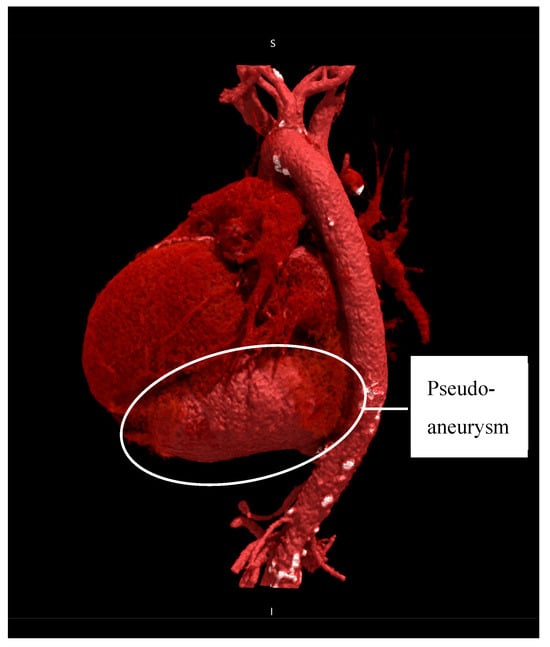

Preoperative TTE showed a moderately dilated LV with a biplane Simpson-derived ejection fraction of 31%. A giant pseudoaneurysm was identified, communicating with the true LV cavity through a broad neck, and containing a mural thrombus. No recurrent pericardial effusion was seen. Additionally, severe functional MR and TR were observed, due to systolic leaflet restriction and annular dilatation. A computed tomography angiography (CTA) illustrated an impressive LV pseudoaneurysm measuring 12.5 × 11.6 × 8.0 cm (Figure 2 and Figure 3).

Figure 2. Cinematic rendering of heart and great vessels illustrating the pseudoaneurysm (12.5 × 11.6 × 8.0 cm) situated below the heart, left lateral view.